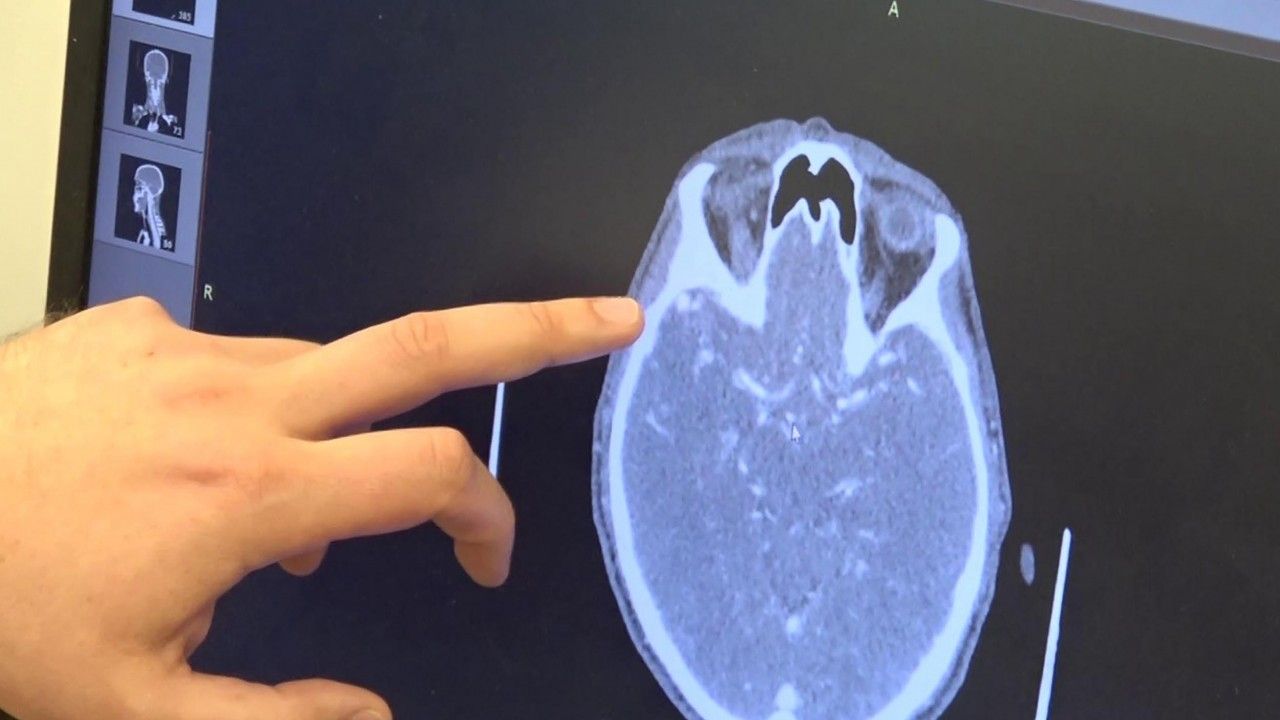

Hastanenin beyin cerrahi kliniğinde ilk kez damar yumağı operasyonu gerçekleştirildiğini belirten Opr. Dr. Eray Serhat Haktan, "3 hafta öncesinde ani şiddetli gelişen baş ağrısı, baş dönmesi ve bulantı şikayeti ile hastaneye müracaat ettiğinde beyin kanaması saptanıyor. Aynı merkezde yapılan anjiyografi işleminde beynin sağ tarafında, halk arasında damar yumağı olarak lezyon saptanıyor. Bunun üzerine hasta Erzurum'a sevk edildi. Yoğun bakım ünitemize aldık. Hastanemizde 7-24 çalışan bir endovasküler ünitesi ve ameliyathanemiz bulunuyor. Bu ameliyathane ünitemizde hastamızı yoğun bakım aldıktan sonra 1-2 saat içerisinde yaptığımız bütün hazırlıklardan sonra hızlıca operasyona hazırladık. Hastayı ameliyathaneye aldık. Yaklaşık 5 saat süren bir operasyonla birlikte sağ tarafta kafatasını açıp beynin içerisindeki damar yumağını başarılı bir operasyonla çıkarttık. Hastamızın tomografisi çekildi. Beyindeki damar yumağının tamamen alındığı görüldü. Bundan sonrasında hastamızı yoğun bakım ünitemize aldık. 2 hafta kadar yoğun bakım ünitemizde yattı. Bir hafta önce servisimize çıkardık. 4 gün önce de tekrar bir kontrolle beyin anjiyografisi işlemini yaptık. Burada da tamamen damar yumağının kapandığını gördük. Sağlığına kavuşan hastamızı taburcu edeceğiz" diye konuştu.